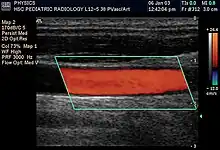

Intravascular ultrasound image of a coronary artery (left), with color-coding on the right, delineating the lumen (yellow), external elastic membrane (blue) and the atherosclerotic plaque burden (green)

In angiology or vascular medicine, duplex ultrasound (B Mode imaging combined with Doppler flow measurement) is used to diagnose arterial and venous disease. This is particularly important in potential neurologic problems, where carotid ultrasound is commonly used for assessing blood flow and potential or suspected stenosis in the carotid arteries, while transcranial Doppler is used for imaging flow in the intracerebral arteries.

Intravascular ultrasound (IVUS) uses a specially designed catheter with a miniaturized ultrasound probe attached to its distal end, which is then threaded inside a blood vessel. The proximal end of the catheter is attached to computerized ultrasound equipment and allows the application of ultrasound technology, such as a piezoelectric transducer or capacitive micromachined ultrasonic transducer, to visualize the endothelium of blood vessels in living individuals.[11]

In the case of the common and potentially, serious problem of blood clots in the deep veins of the leg, ultrasound plays a key diagnostic role, while ultrasonography of chronic venous insufficiency of the legs focuses on more superficial veins to assist with planning of suitable interventions to relieve symptoms or improve cosmetics.